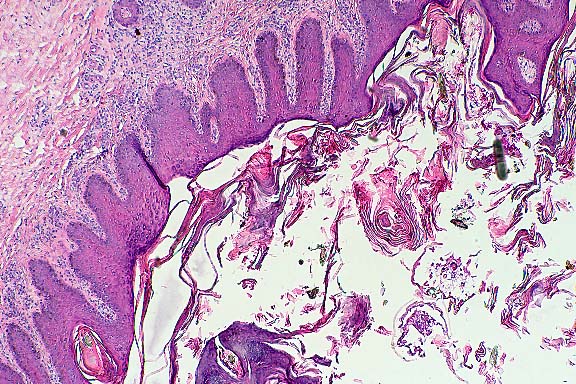

Case 4: Haired skin. Demonstrates sloughed keratin scale which surrounds the outlines of 2 mites cut in medial section (appendages, chitinous exoskeleton visible). Epidermis is acanthotic with parakeratotic hyperkeratosis and a lymphohistiocytic infiltrate of the superficial dermis. (4x obj).

AFIP Diagnosis: Haired skin: Dermatitis, proliferative, superficial, perivascular, chronic-active, diffuse, moderate, with severe orthokeratotic and parakeratotic hyperkeratosis, intracorneal pustules, and mites.

Conference Note: In some of the sections examined in conference, there were one or more cross-sections of an ectoparasite within the hyperkeratotic crust. The organism has jointed appendages with prominent setae, striated muscle, and mouth parts. This case was reviewed by Chris Gardiner, PhD, veterinary parasitology consultant to the AFIP. He confirmed that the organisms are mites but was unable to provide a more specific classification.